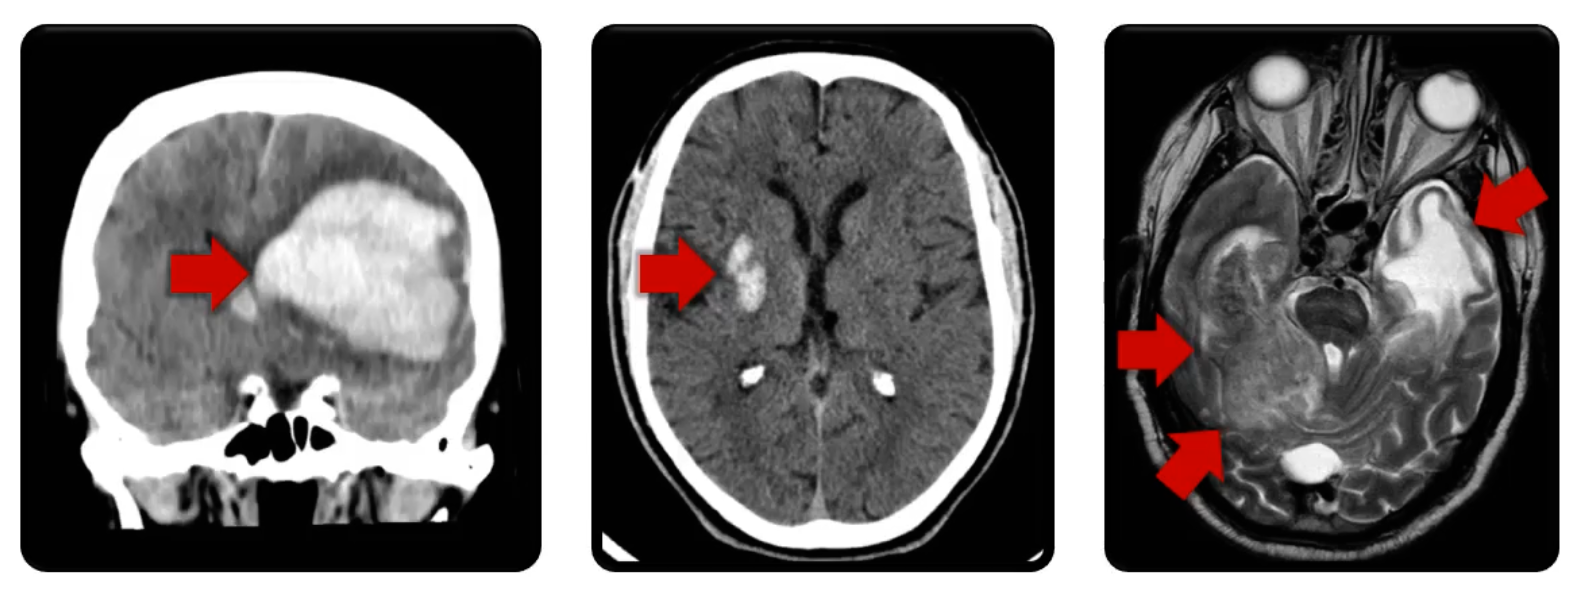

Intracranial Hem.

Hemorrhage stroke

ruptured vessels

Can result in edema, mass effect, and limited blood supply

Traumatic Contusions

Intracranial bleeding

caused by trauma

can appear with other hemorrhage injuries

can cause neurologic deficits